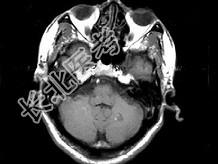

- 单项选择题男,49岁, 右侧肢体无力10余天,伴头昏行走不稳, 根据所提供图像,最可能的诊断是 ( )

E、颅内多发海绵状血管瘤